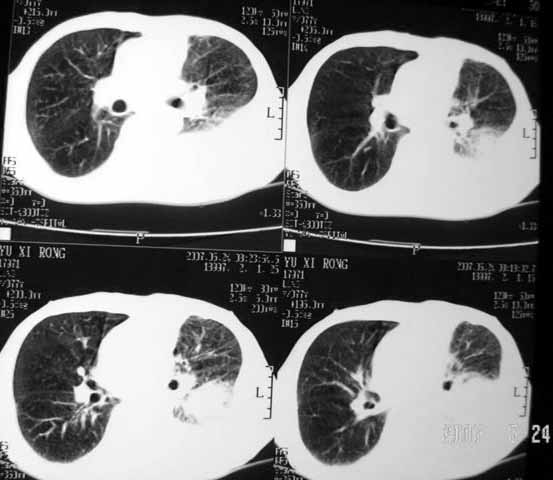

以下是引用luochengyi在2007-5-24 14:33:00的发言:[br]考虑左下肺癌。左侧胸腔积液。

以下是引用adams在2007-5-24 17:12:00的发言:[br]支持“考虑左下肺癌,左侧胸腔积液,建议胸水检查”。[br] [br]

以下是引用fumaogui在2007-5-24 16:20:00的发言:[br]左侧胸腔积液.[br]左下叶不张考虑中心型肺癌[br]建议纤支镜检查.